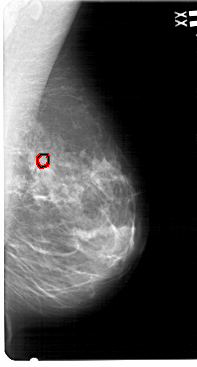

A_1546_1.LEFT_CC

LEFT_CC LINES 5101 PIXELS_PER_LINE 2791 BITS_PER_PIXEL 12 RESOLUTION 43.5 NON_OVERLAY

FILE: A_1546_1.RIGHT_CC.OVERLAY

TOTAL_ABNORMALITIES 1

ABNORMALITY 1

LESION_TYPE CALCIFICATION TYPE PLEOMORPHIC DISTRIBUTION CLUSTERED

ASSESSMENT 4

SUBTLETY 1

PATHOLOGY BENIGN

TOTAL_OUTLINES 1

BOUNDARY